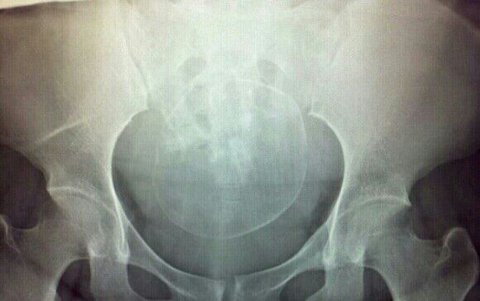

전좀특별하게ㅎㅎ 저희애 임신33주때 골반뼈 찍느라구 어쩔수없이 찍었던 엑스레이사진이에요ㅋ 골반사이로 머리가 쏙 자리잡아있는..ㅎㅎ